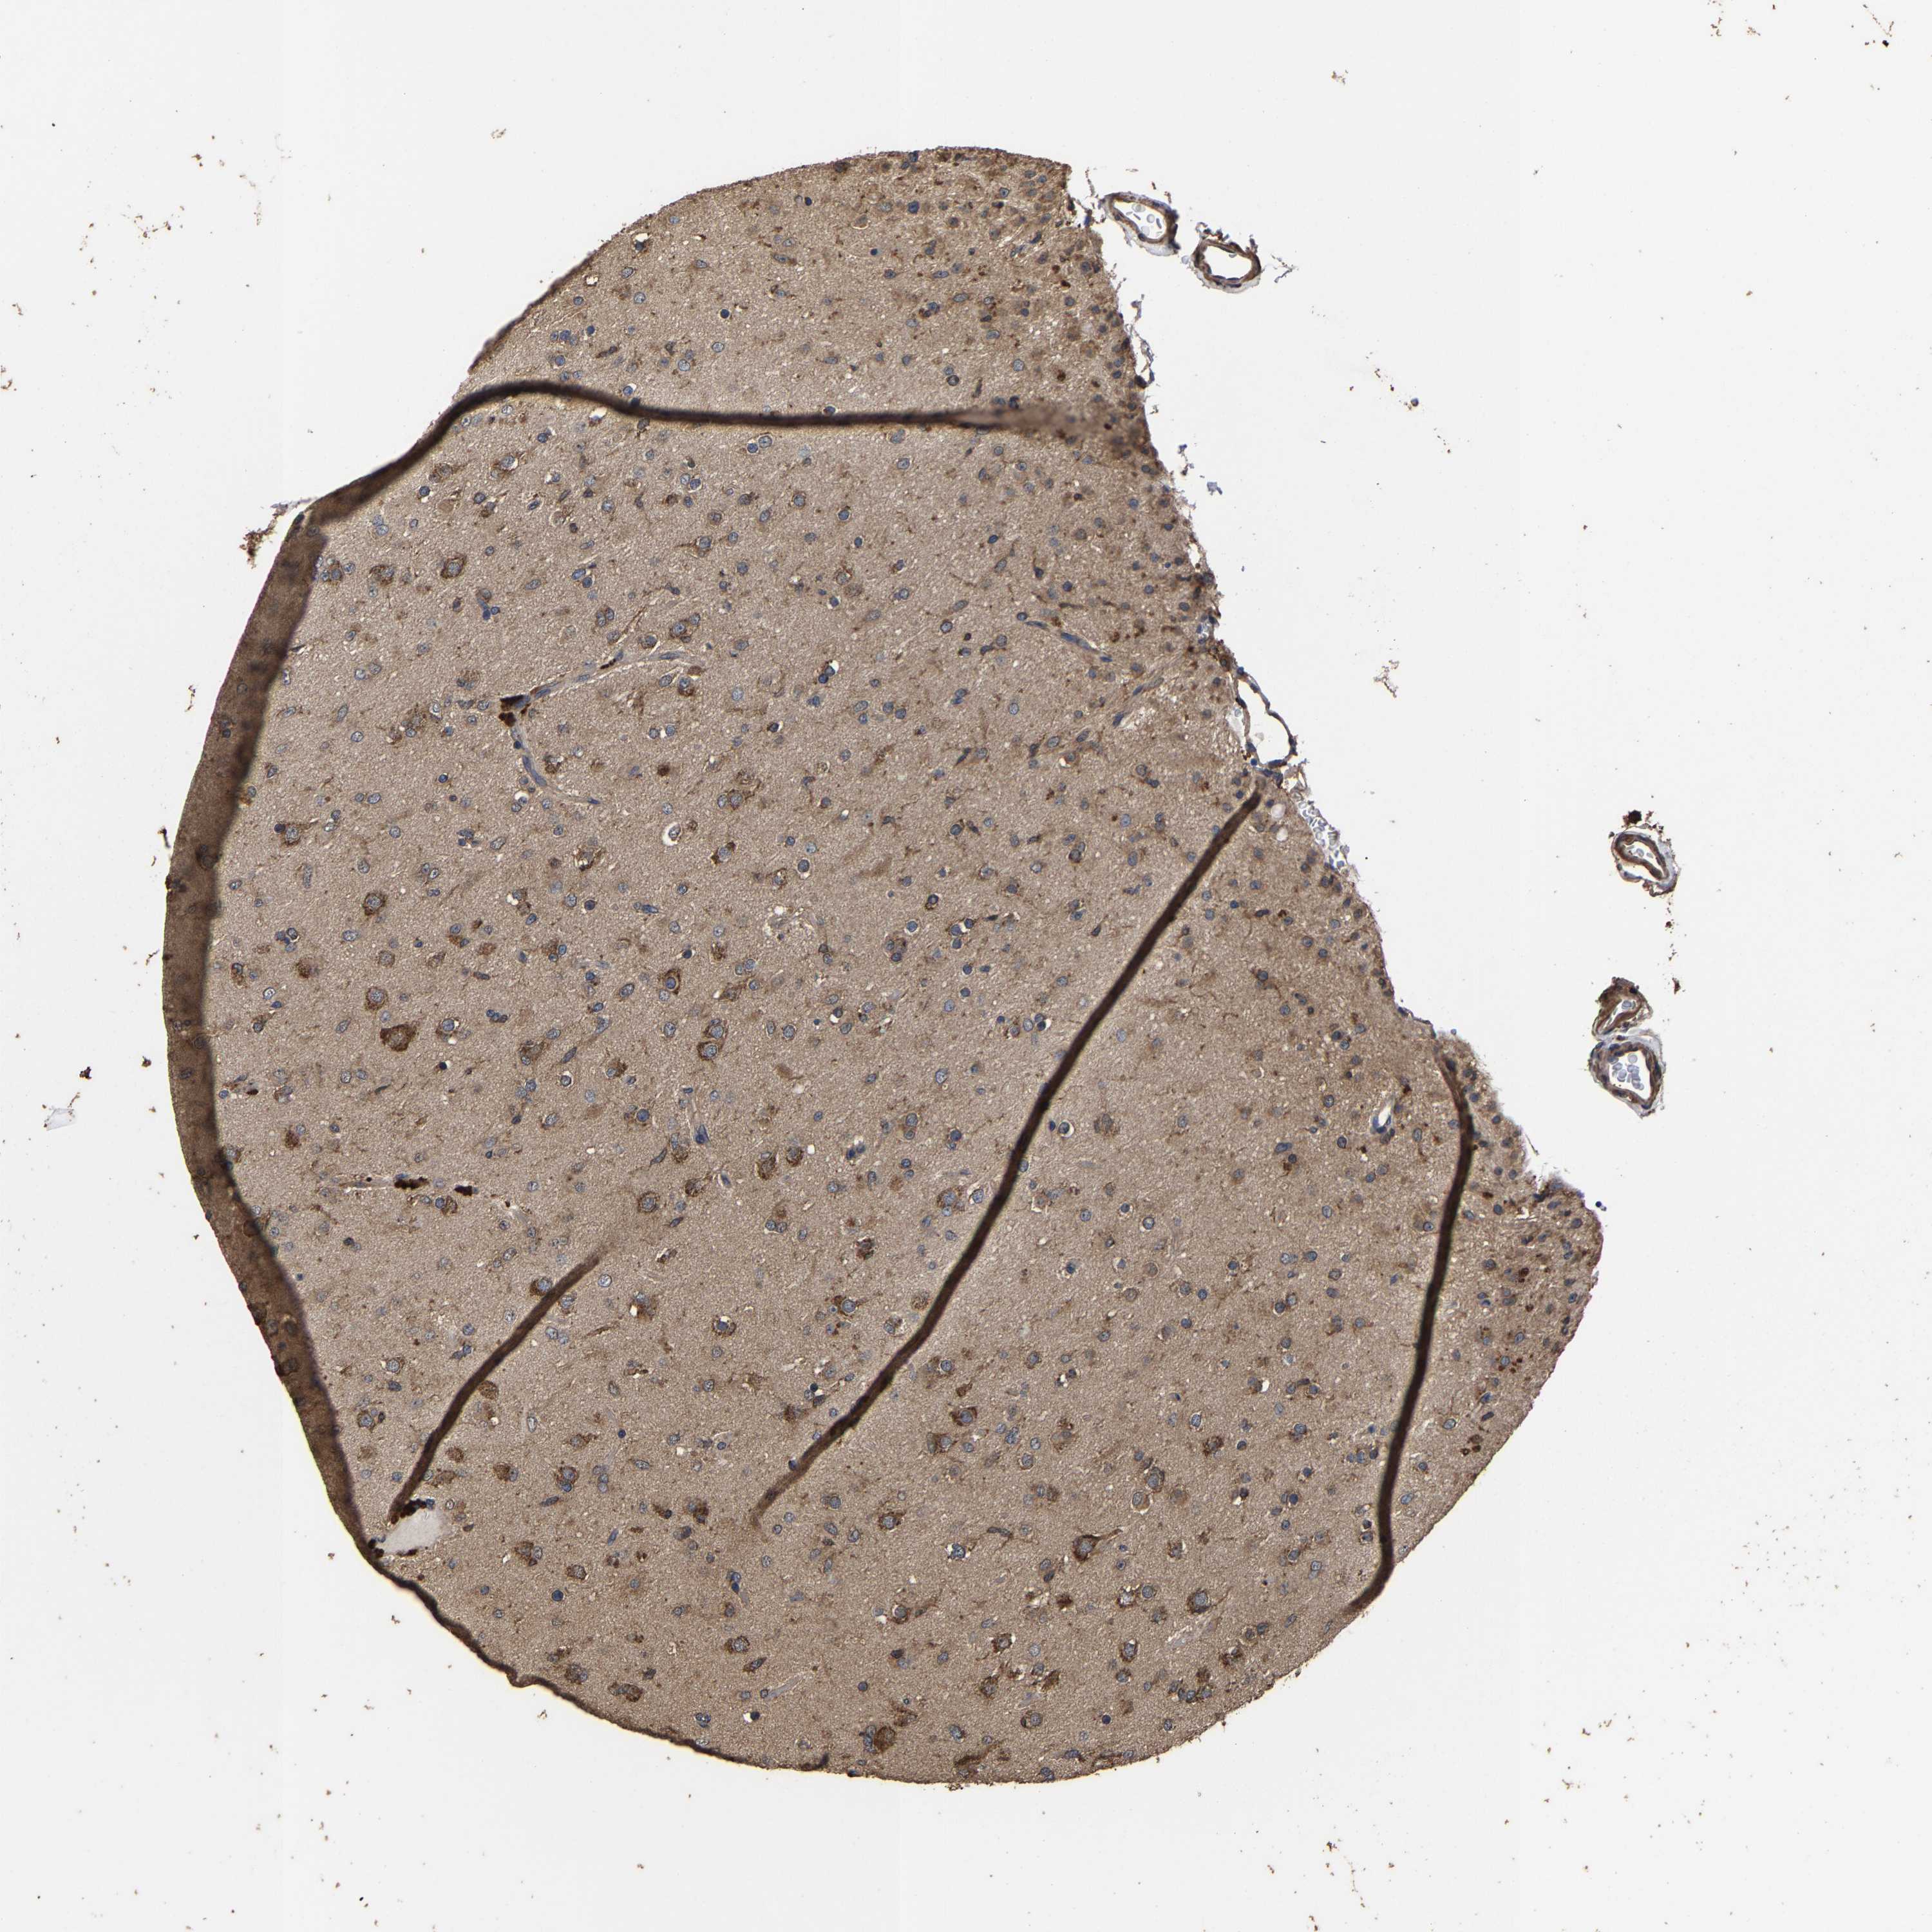

GLIOMA - Protein expressioni

A mouse-over function shows sample information and annotation data. Click on an image to view it in a full screen mode. Samples can be filtered based on level of antibody staining by selecting one or several of the following categories: high, medium, low and not detected. The assay and annotation is described here.

Note that samples used for immunohistochemistry by the Human Protein Atlas do not correspond to samples in the TCGA dataset.

Antibody stainingi

Antibody staining in the annotated cell types in the current human tissue is reported as not detected, low, medium, or high, based on conventional immunohistochemistry profiling in selected tissues. This score is based on the combination of the staining intensity and fraction of stained cells.

Each image is clickable and will lead to virtual microscopy that enables deeper exploration of all samples and also displays staining intensity scores, fraction scores and subcellular localization as well as patient and tissue information for each sample.

Antibody HPA021126

Staining

High

Medium

Low

Not detected

Intensity

Strong

Moderate

Weak

Negative

Quantity

>75%

75%-25%

<25%

None

Location

Nuclear

Cytoplasmic/membranous

Cytoplasmic/membranous,nuclear

Glioma, malignant, High grade

Glioma, malignant, Low grade